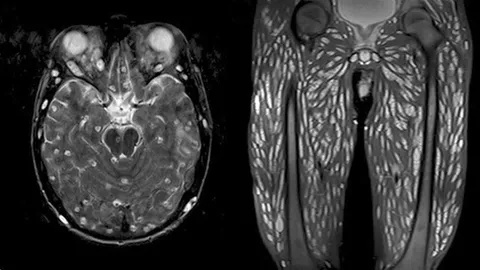

แพทย์ตะลึงพบไข่พยาธิตัวตืดในสมองหนุ่มใหญ่ชาวอเมริกัน หลังปวดหัวเหมือนไมเกรน